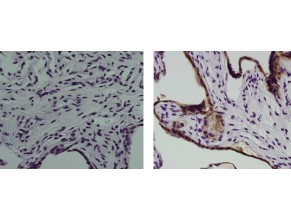

Description: The monoclonal antibody 8B6 recognizes human Placental Alkaline Phosphatase (PLAP), a 130 (or 130 with 65 kDa) enzyme expressed by placental syncytiotrophoblastoid cells. This enzyme has slightly different enzyme kinetics from other phosphatases. PLAP can be found anchored to the plasma membrane in addition to the cytoplasm. Expression is found in several germ line cancers; ovarian and testicular. Expression is also present in human embryonic stem cells and bone marrow-derived mesenchymal stromal cells.

This 8B6 antibody reacts with both the Regan and Nagao isozymes.